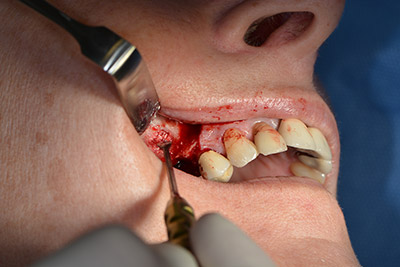

The next step was the sinus floor elevation with simultaneous implantation. The Implantmed also had a presetting at the first position for the buccal fenestration of the maxillary sinus wall.

The fenestration was prepared at 35,000 rpm and then the nasal mucosa were prepared in the cranial direction (Fig. 13 to 14).

The implant was then placed and the bone built up. In this case, because of the size of the augmentation region, autologous bone chips, harvested with an osseous trap as drilling chips from implantation 16 and fenestration 14, were mixed with bone replacement material.